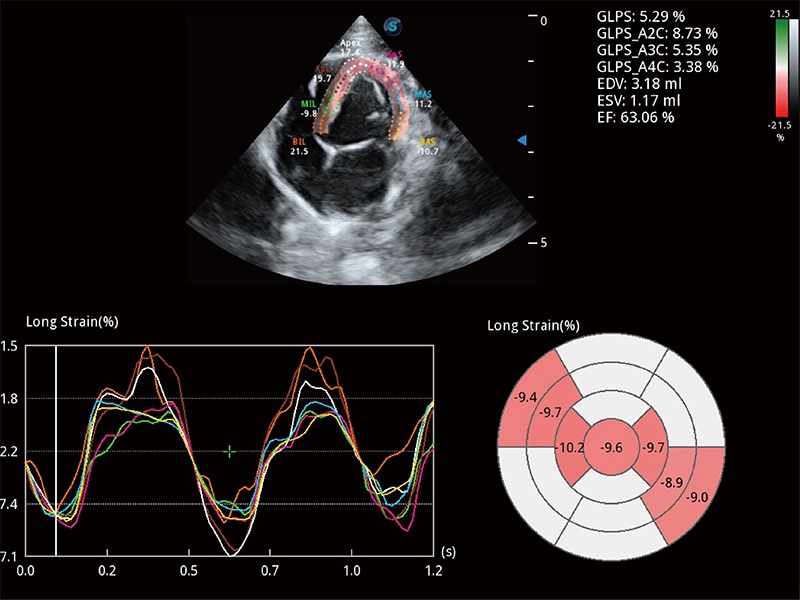

• MQA 心肌定量分析

通过心肌识别技术与二维斑点追踪技术相结合,对心脏的超声图像进行量化分析。计算心肌17个节段的应变、应变率、速度、位移等,并通过牛眼图的形式进行呈现。

优异的基础图像

ProPet 80 全新的动物超声智能软件和丰富的探头群,为动物医生提供了高清晰度和精细分辨率的图像,无论在宠物、马科、畜牧还是实验室动物等应用中都可以轻松应对,为您的日常工作带来满意的体验。

(犬)四腔心MQA